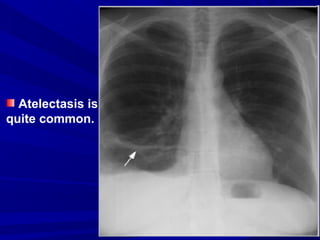

Atelectasis is

quite common.

(1) Chest x-ray findings, non specific, may

include:

• Normal

• Diaphragm elevation